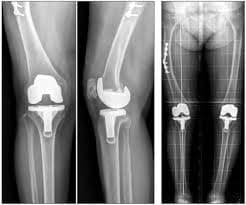

Өвдөгний үе бүтэн солих мэс засал (TKA) image3

Бэхэлгээт загвар

Бэхэлгээт загварын хиймэл үе жингийн илүүдэлгүй, амьдралын идэвхи багатай хүмүүст илүү тохиромжтой ихэвчлэн настай хүмүүст хийгддэг. Булуу болон шилбэ ясны хоорондох полиэтилен жийргэвч шилбэний импланттай хөдөлгөөнгүй бэхэлгээтэй байдаг.